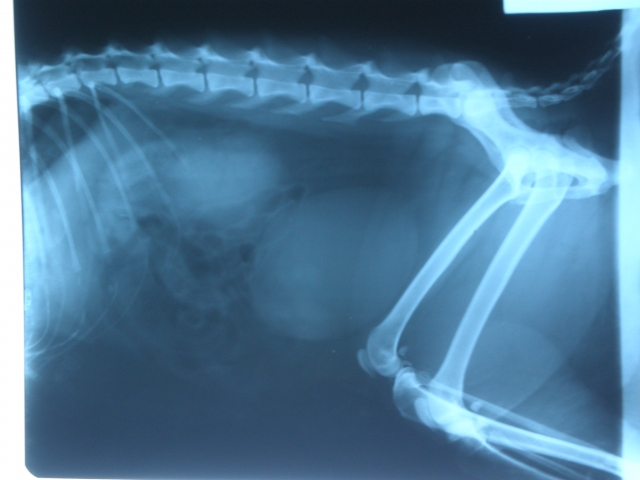

혈액검사와 X-Ray, 또 다른 검사들을 마친 후 신장의 건강도를 측정하는 수치들이 거의 최악 수준이라고 하십니다.

경아는 심각한 신부전증으로 인해 배뇨를 원활히 할 수 없어서 방광에 소변이 가득 찬 상태고,

그 뇨독으로 인해 입 안에도 염증이 발생한 거라고 하십니다.

X-Ray 로 본 경아의 방광에 소변이 가득 차서 그 날 밤을 넘겼다면 방광이 터졌을 가능성이 높다고 하십니다.